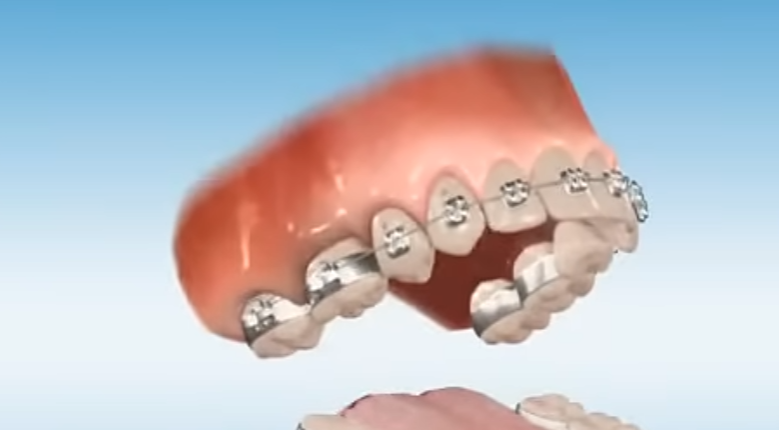

basically if orthodont only removes your UPPER 4th 2 molars will it still recess you? (in overbite case) because i heard people completely have their bone structure fallen because of upper and lower jaw molar extractions. i dont need extractions from both, just 2 4th molars from upper jaw. thanks